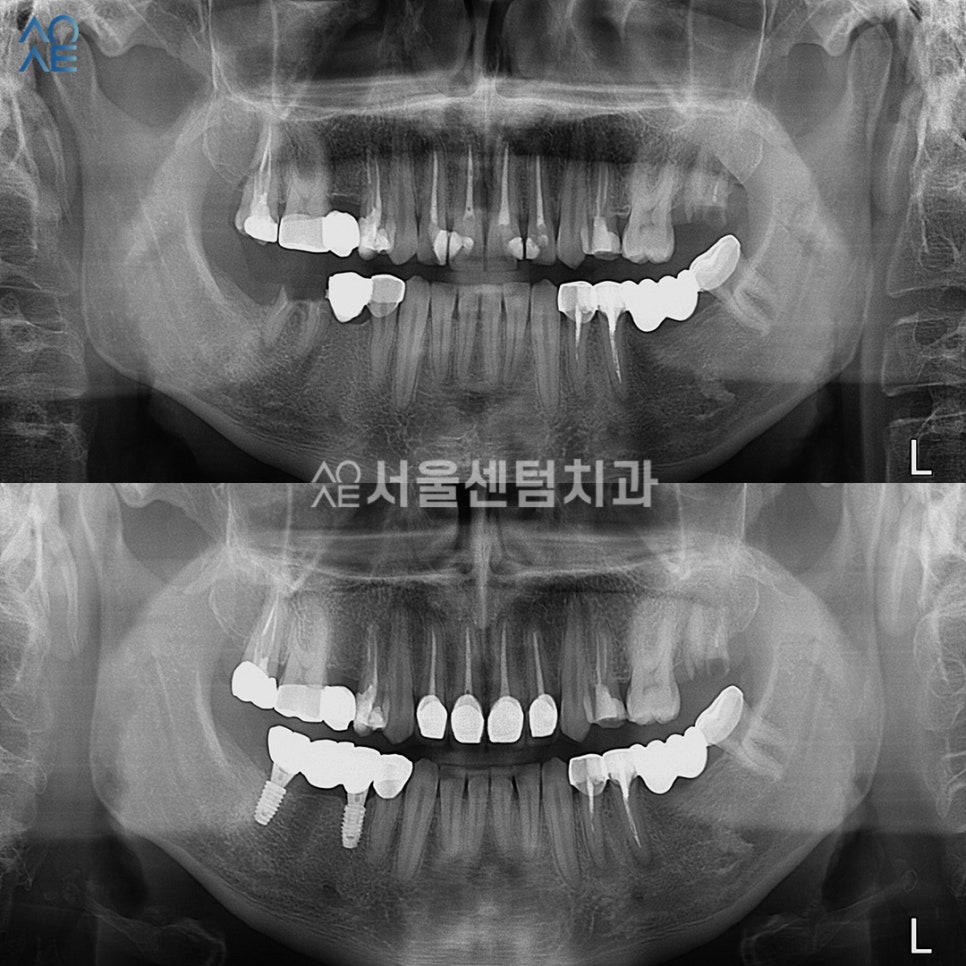

20대임플란트 수술한 부위가

잘 아물 때까지 기다리는 동안에

환자분이 원하셨던 앞니 치료도 진행했습니다.

기존 충전 재료를 모두 제거하고

새롭게 생긴 2차 충치를 치료하였습니다.

이후에 지르코니아 보철물도 수복하고요.

임플란트수술 경과도

꾸준히 잘 체크했습니다^^

첫 임플란트를 수술하고 나서

원래는 많이 내원할 필요는 없지만

이 환자분의 경우엔 추가 치료가 있다보니

임플란트 크라운을 올리기까지

9번 정도를 내원했던 것 같습니다.

덕분에 경과 체크도 꼼꼼하게 할 수 있었고

크라운도 잘 제작하여 수복해드렸습니다.

20대임플란트 완성

왼쪽(사진상 오른쪽)에도 깨진 치아가 있어서

함께 치료를 권유 드렸지만

환자분의 일정 상의 이유로 잠시 보류되었습니다.

그래도 다른 치료들은 모두

무사히 마칠 수 있었습니다.

특히 앞니가 심미적으로 많이 개선되어

마음에 들어하셨습니다.